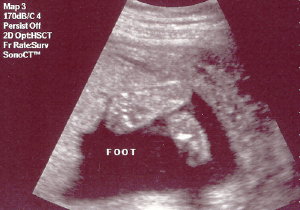

My Latest Ultrasound.... I just had an ultrasound on Tuesday, July 11th. I was so excited that all ate that morning was a Chewy Granola Bar. The ultrasound was at 1:00 p.m., so during the ultrasound, I almost fainted. The room started to go black. My body temperature felt like it was dropping, BUT I broke out in a sweat, and the sound drained from the room. All I could do was grab Duane's hand, as if holding on for my dear life. Go figure. Can anybody say "low blood sugar." Oh well. My husband gave me the whole lecture on how breakfast is the most important meal of the day, etc.... So you can all save your preaching for another day, thank you very much. Other than that, the whole day was so exciting! WE'RE HAVING A BOY! Here are some ultrasound pictures for you. Sorry they're not that clear but it's better than nothing, right? Enjoy...